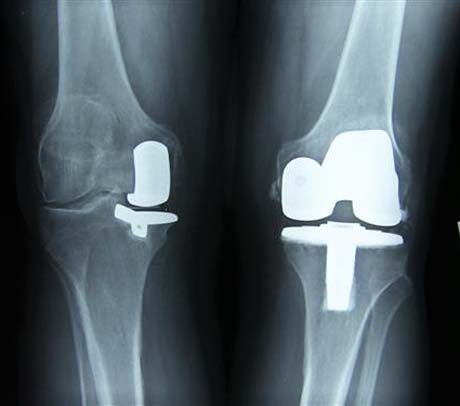

Ακτινολογική εικόνα της μονοδιαμερισματικής αρθροπλαστικής. Το υγιές τμήμα της άρθρωσης παραμένει ανέπαφο.

Άμεση σύγκριση της ολικής και της μονοδιαμερισματικής αρθροπλαστικής γόνατος.

Μονοδιαμερισματική αρθροπλαστική Oxford Zimmer Biomet για την αντικατάσταση του έσω διαμερισματος της άρθρωσης του γόνατος το οποίο πάσχει από οστεοαρθρίτιδα.